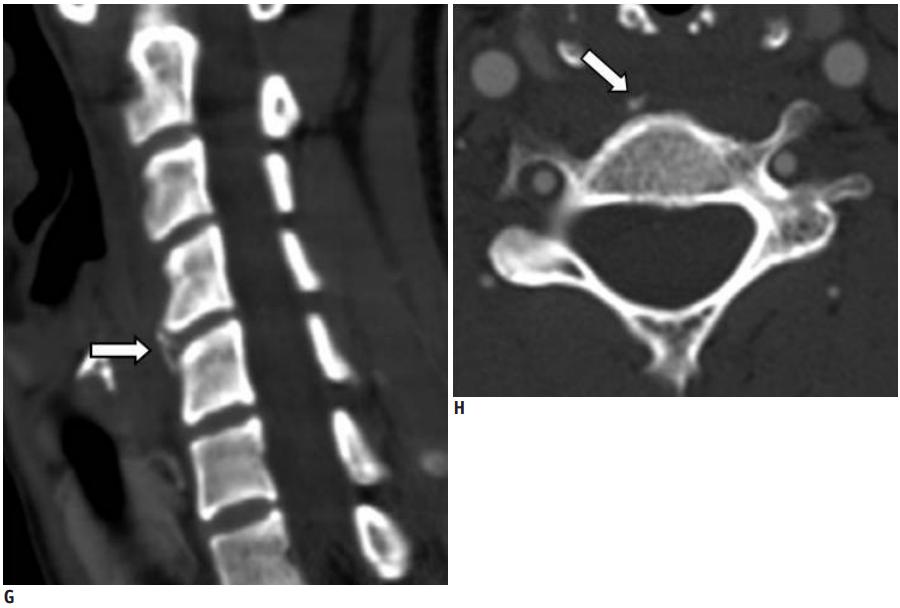

明确诊断主要通过影像学方法,颈椎CT是关键。 颈长肌钙化性肌腱炎特异性的影像表现是C1-4椎体前缘软组织肿胀和积液与C1椎体前弓下方不规则钙化沉着共存。

CT的高分辨率能够明确肌腱内的钙化,能够明确是钙化而不是其他骨骼来源的高密度影。 钙化一般位于寰椎前弓的下方和枢椎齿状突的前方,少部分可位于下颈椎前侧 。CT有助于明确椎体前积液的存在和排除其他病理表现,如骨折或脓肿。MRI对诊断不是必须,但有时可帮助确定软组织异常,排除咽后脓肿,脊椎炎或肿瘤。 MRI检查T2加权在椎前可见局限性的裂隙样区域,大多位于C1-4水平,呈高信号改变,这反应是由于炎症引起的积液 。T2加权、脂肪抑制序列和T1加权对鉴别积液和脂肪组织、含脂肪的骨髓以及咽后感染、脊椎炎有重要作用。MRI检查在钙化检查方面存在不足,T2加权呈低信号。

上述病人,E为增强,F为抑制像,G和H:经非甾体抗炎药治疗3天后查颈椎CT示C4-5椎前无定形钙化。

上述病人,I和J: 入院4天后复查颈椎MRI示椎前积液明显减少; K,随访2个月复查CT示C4-5前钙化灶减小。(PMID: 21852912)